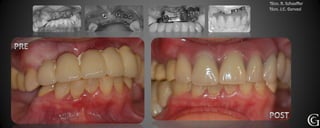

Prótesis Fija Convencional

Restauraciones periféricas totales “coronas”

Las coronas son restauraciones que involucran la totalidad del

diente, confeccionadas fuera de la boca (indirectas totales) que

luego son adheridas al diente en tratamiento. Pueden ser de

diversos materiales, cerámicas, composite y/o metálicas.

Técn. R. Schaeffer

PRE

Prótesis Fija Convencional Restauracionesperiféricas totales “coronas” Las coronas son restauraciones que involucran la totalidad del diente, confeccionadas fuera de la boca (indirectas totales) que luego son adheridas al diente en tratamiento. Pueden ser de diversos materiales, cerámicas, composite y/o metálicas.

PRE Técn. R. Schaeffer